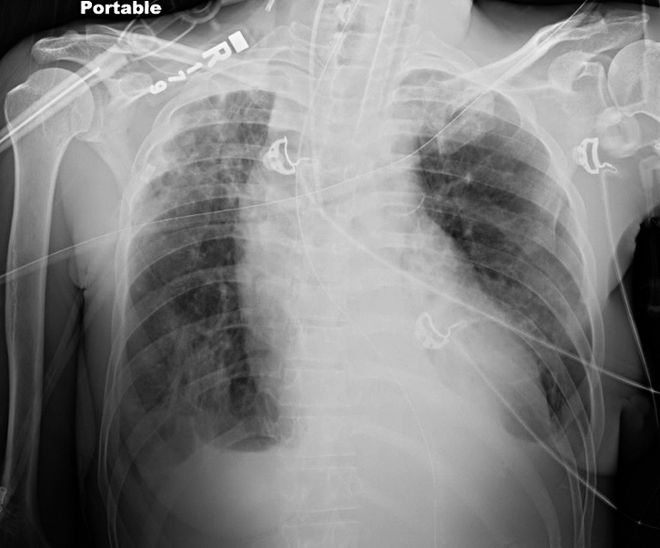

经食管下括约肌肉毒杆菌毒素注射治疗后,食管持续维持减压状态(图5),患者可安全经口摄入流质食物,康复出院。